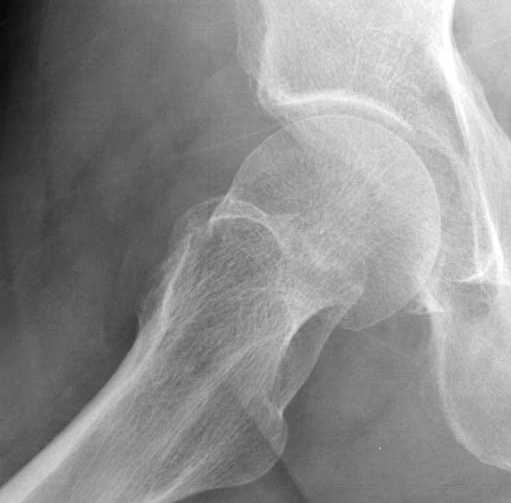

Почему неполный перелом? Я бы назвал его вколоченным!

Well, it should be fractured even if you do not see the whole fx line.

Перелом конечно не вколоченный т.к. видно линию перелома и нет суперпозиции костной ткани.

Добрый день. Перелом коварный. Через время может произойти лизис в области "неполного" перелома и он превратиться в "полный" со всеми очевидными проблемами, тем более у пациента, склонного к питию. Если не разовьется делирий или после выхода из него, рекомендую внутренний остеосинтез винтами.

Профилактику дальнейшего раскола неполного перелома шейки провели тремя канюлированными шурупами.